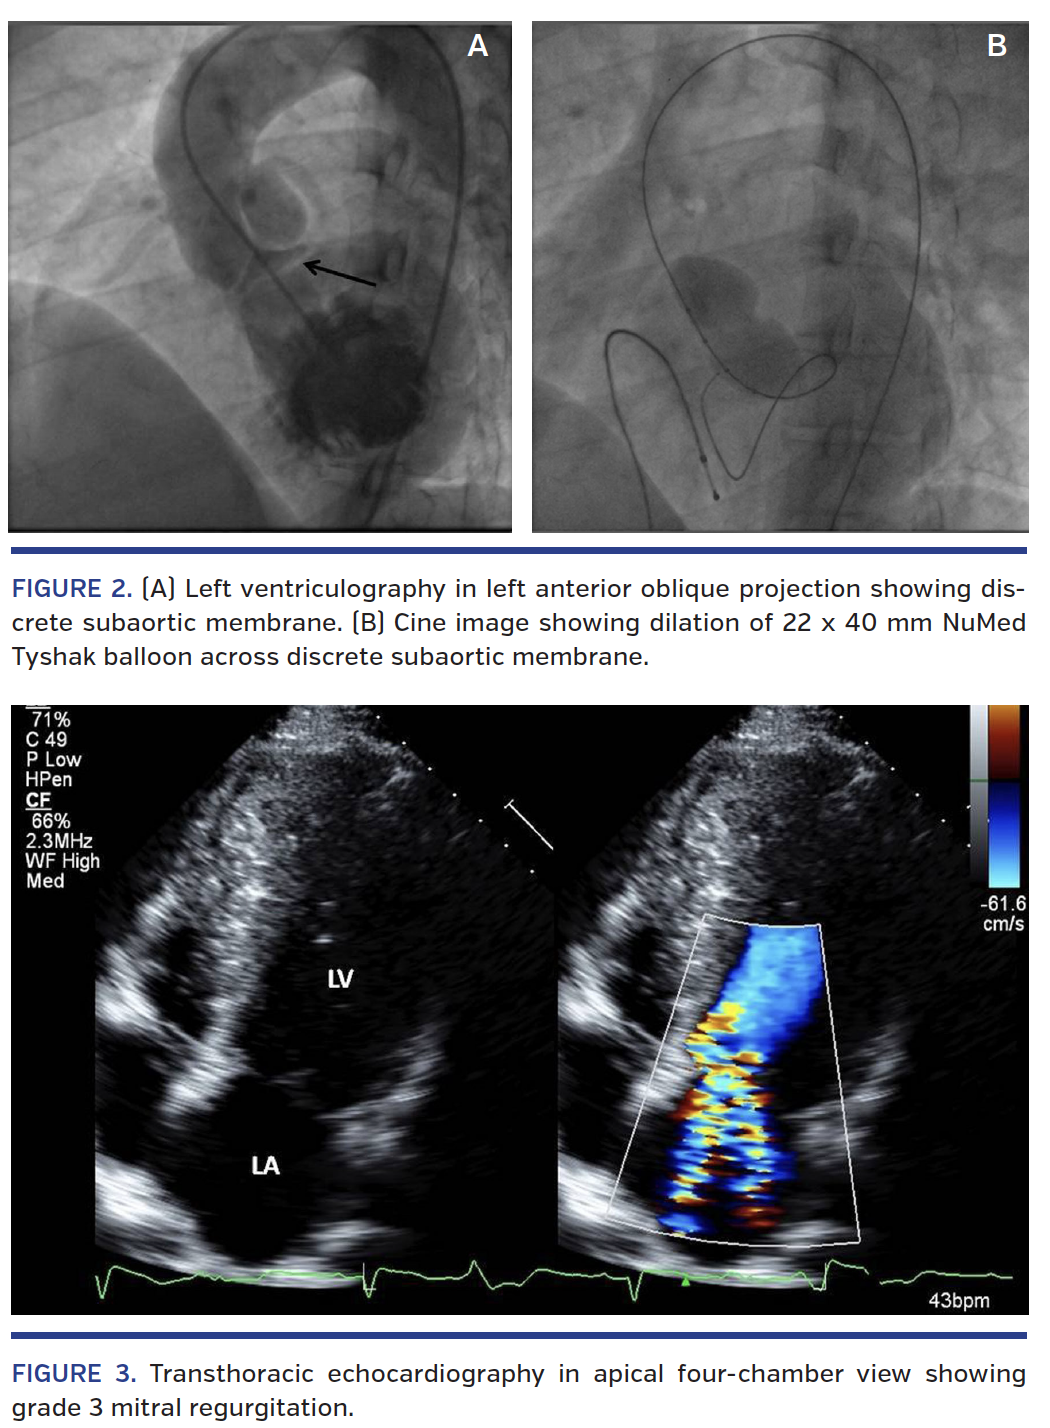

Left ventricular angiography showed discrete thick subaortic membrane forming a triangular chamber just below the aortic valve (Figure 2A; Video 2); therefore, balloon dilation was planned. Baseline gradient across the membrane was 118 mm Hg and aortic annulus measured 24 mm. The first attempt to dilate the membrane failed due to insufficient length of coiled wire and Inoue balloon. The membrane was then crossed with a Terumo wire, which was exchanged with an Amplatzer extra-stiff wire. The membrane was dilated with an 18 x 40 mm NuMed Tyshak balloon (B. Braun) (Figure 2B; Video 3). Following the first inflation, the residual systolic gradient across the LVOT was 80 mm Hg, so subsequent dilation was done with a 22 x 40 mm NuMed Tyshak balloon. Residual LVOT gradient after two dilations was 5 mm Hg. There was no evidence of aortic regurgitation. Repeat transthoracic echocardiography at 24 hours showed recurrence of severe LVOT gradient. There was no aortic regurgitation. However there was grade 2-3 mitral regurgitation (Figure 3; Video 4) secondary to chordal rupture. Surgical membrane resection and repair of ruptured chordae were advised.

Percutaneous balloon dilation can cause papillary muscle rupture, resulting in severe mitral regurgitation and pulmonary edema.7 In our patient, the balloon dilation caused rupture of chordae, resulting in grade 2-3 mitral regurgitation. The relief of subaortic stenosis was transient and the initial result could be due to stretching of subaortic membrane, which recoiled later resulting in recurrence of stenosis.